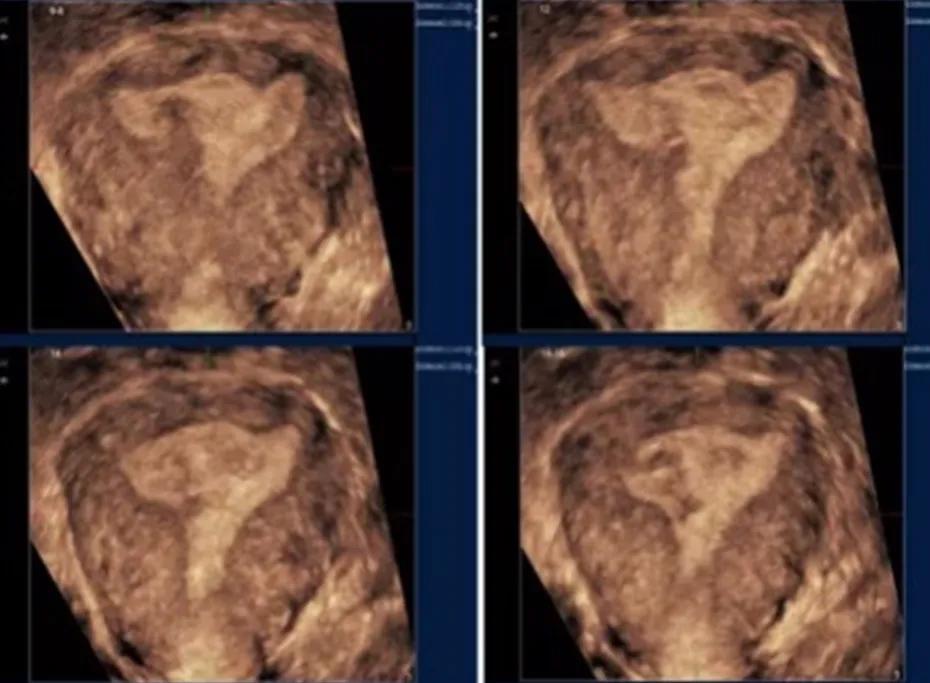

经阴道三维超声检查,一般是在常规阴道超声检查的基础上加做,通俗的理解,就是立体超声。相比常规阴超,三维超声可以全方位,多切面,多角度来观察子宫内膜及宫腔的环境,可以提供更多的诊断信息。其中最有价值的切面就是冠状切面。同时实时三维能够旋转,从每个切面成像,可以准确,迅速的获得丰富立体的子宫内膜完整图像信息,更利于诊断准确性的提高,与传统的子宫输卵管造影比较,具有更好的实用价值,更得到临床工作中的认可。

三维超声表现

当发生宫腔粘连时,中央性粘连表现为内膜的缺损,回声不均匀等,周围性粘连则可能变现为倒三角形结构的破坏,宫底部或双侧壁的不对称,宫角圆顿,宫腔缩窄,内膜及基层分界不清晰,不规整等。